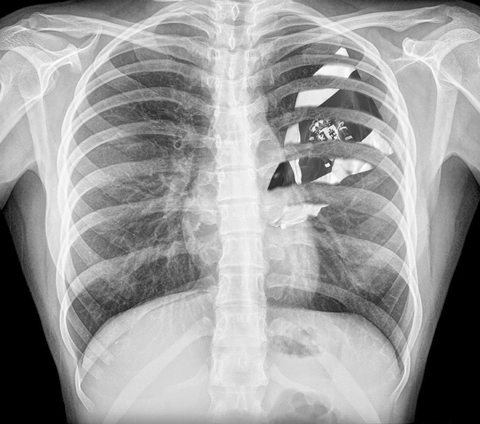

Se tienen convenios de colaboración para la realización de diversos estudios de gabinete con proveedores certificados para: